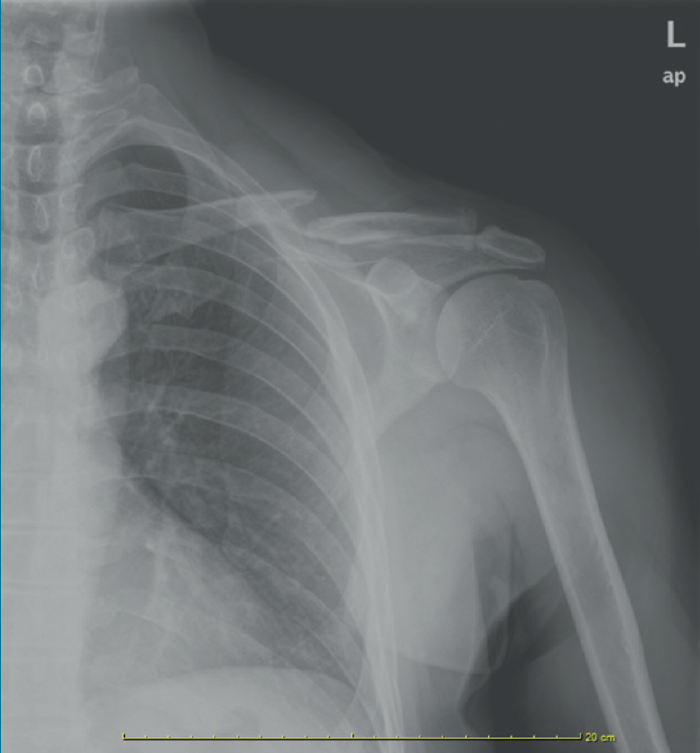

Las fracturas del tercio medio de la clavícula suponen el 5-10% de las fracturas del adulto y el 40% de las fracturas del hombro.

Su desplazamiento va a depender de la tracción que ejerzan los músculos que se insertan en ella: el esternocleidomastoideo, el pectoral mayor y el dorsal ancho(1) (Figura 1).

retla.05109.fs2202008-figura1.png

Figura 1. Fractura del tercio medio de la clavícula.